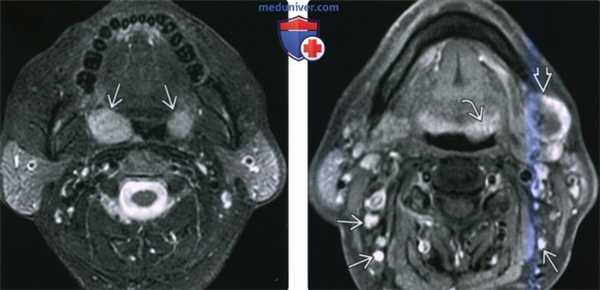

(Слева) На аксиальной КТ с КУ у ребенка со СПИДом определяется массивная аденоидальная НХЛ с неравномерным накоплением контраста. Обратите внимание на крупный заглоточный лимфоузел слева и практически полную окклюзию просвета носоглотки. Обе верхнечелюстные пазухи и полость носа заполнены секретом (доброкачественные изменения).

(Справа) На аксиальной КТ с КУ определяется мультифокальная НХЛ с вовлечением миндалины справа и лимфоузла II уровня с экстранодальным распространением. Шейная лимфаденопатия присутствует более чем в 50% случаев НХЛ слизистой оболочки глотки (СОГ).

2. КТ при неходжкинской лимфоме слизистой оболочки глотки:

• КТ с КУ:

о Массивная опухоль с минимальным накоплением контраста, заполняющая просвет глотки:

- Часто без глубокого распространения в окружающие ткани

о Сопутствующее поражение лимфоузлов НХЛ наблюдается в 50% случаев:

- Лимфоузлы обычно увеличены, >2 см, без признаков некроза

- В случае НХЛ высокой степени злокачественности в центре лимфоузла может обнаруживаться участок некроза:

В особенности при НХЛ, связанной со СПИД